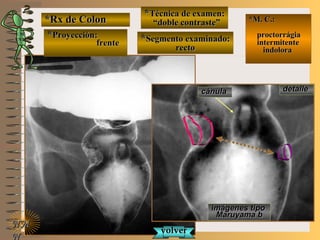

frentefrente

““doble contraste”doble contraste”

““mucosografía”mucosografía”

panorámica ypanorámica y

cuerpo gástricocuerpo gástrico

A-A-El examen es normal o patológico?El examen es normal o patológico?

Examen normal de estómago panorámico yExamen normal de estómago panorámico y

de cuerpo gástrico con técnicas de : A- doblede cuerpo gástrico con técnicas de : A- doble

contraste (relieve interno fino)contraste (relieve interno fino) , B- mucosogra-, B- mucosogra-

fía (tiene por objetivo reconocer el relieve internofía (tiene por objetivo reconocer el relieve interno

grueso = a pliegues) en proyección de frentegrueso = a pliegues) en proyección de frente

B-B-Puede describir la o las imágenesPuede describir la o las imágenes

**OpciónOpción

de volverde volver

a ver lasa ver las

imágenesimágenes

En estas radiografías en proyección de frente seEn estas radiografías en proyección de frente se

deben distinguir: 2deben distinguir: 2 curvaturas (menor y mayor),curvaturas (menor y mayor),

4 segmentos (techo, cuerpo, fondo y antro gástri-4 segmentos (techo, cuerpo, fondo y antro gástri-

co) con el trazado de 3 líneas. Se puede precisarco) con el trazado de 3 líneas. Se puede precisar

la presencia de pliegues gástricos de cara anteriorla presencia de pliegues gástricos de cara anterior